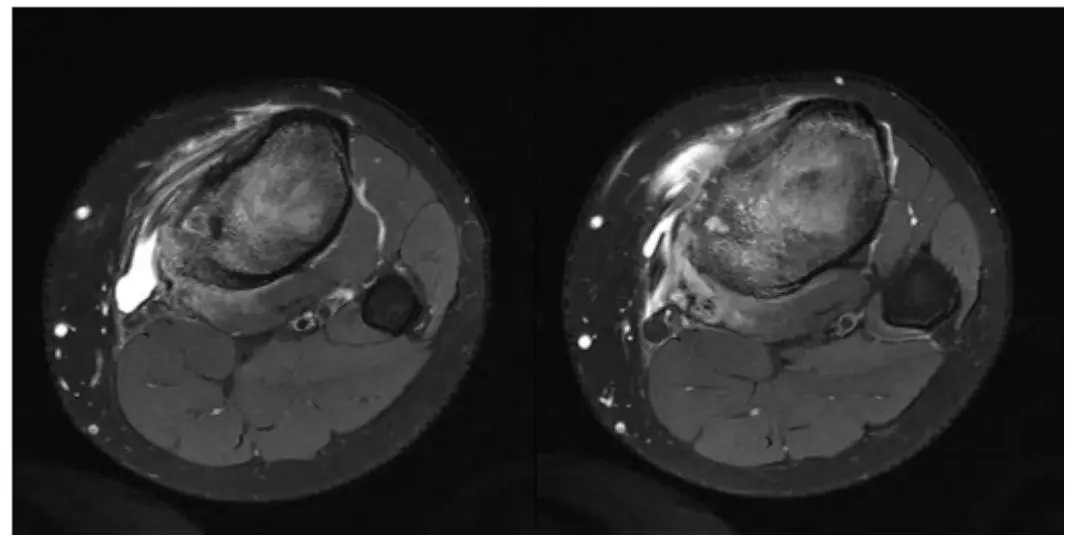

患者没有骨样骨瘤的典型夜间疼痛, 大家讨论一下诊断和鉴别诊断.

ct:股骨见骨样骨瘤病灶

【每周读片】骨样骨瘤

(骨样骨瘤)